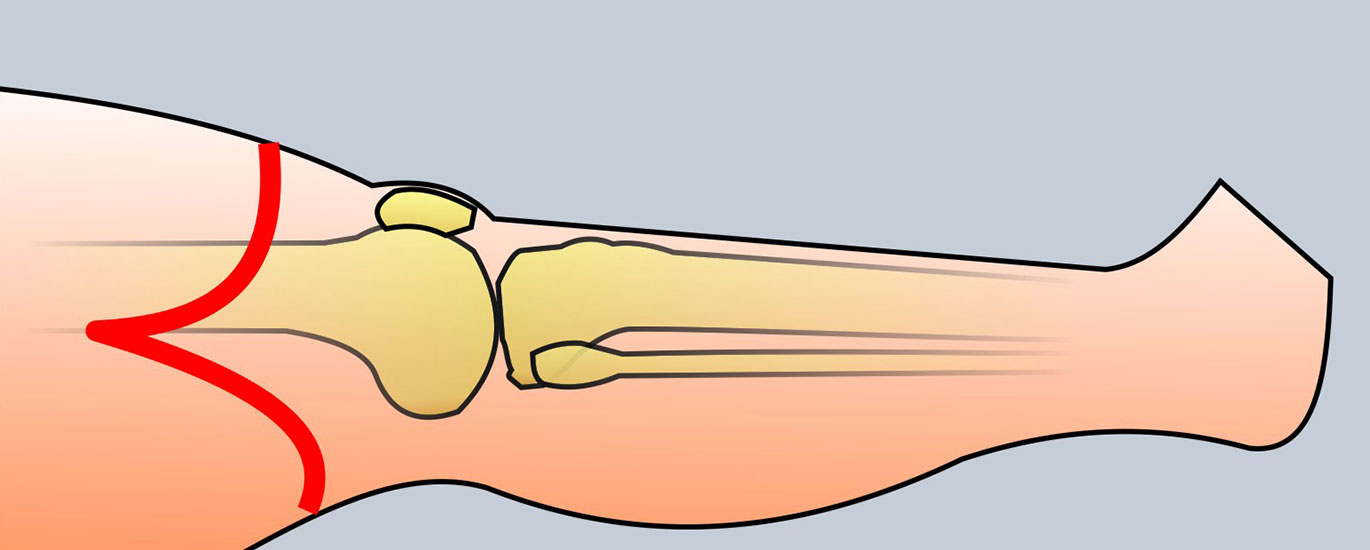

Problematik des nicht antagonisierten Sehnenzugs nach Lisfrancamputation. Die  Fußhebung ist ausgefallen. Durch Zug des M. trizeps surae resultiert eine Spitzfußstellung, die bei Neuropathie ein chronisches Ulkus im Bereich der Hauptbelastungszone hervorr

Abbildung 42

Cave!

Wird der Fußheber desinseriert, kommt es häufig zu einem Spitzfuß mit Stumpfulkus (Abb. 42). Die Prophylaxe und Behandlung bestehen in der Achillessehnendurchtrennung (entspr. Abb. 50). Eine Refixation der Fußhebersehne ist bei vorhandenem Stumpfulkus infektionsgefährdet und nicht erfolgversprechend. Besteht ein Spitzfuß über viele Monate, ist dieser regelmäßig durch eine Arthrofibrose fixiert. Dann müssen alle am Unterschenkel dorsal verlaufenden Sehnen durchtrennt, das Gelenk offen arthrolysiert und die 0-Grad-Stellung temporär mit einem K-Draht fixiert werden. Alternativ ist eine Arthrodese im oberen evtl. auch unteren Sprunggelenk möglich.